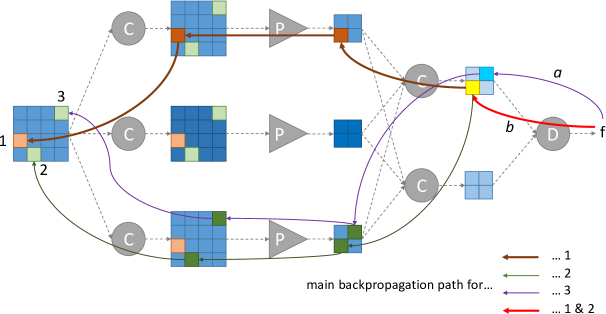

Because those heatmaps depend on backpropagated quantities, the network parameters cannot be optimized using the usual backpropagation method, so a different ConvNet training method had to be proposed: while standard training algorithms propagate image intensities through the ConvNet and backpropagate the gradients of the optimization criterion, the proposed training algorithm involves a third pass on the ConvNet to propagate second-order derivatives forward. This new training procedure can be obtained through simple adaptations of deep learning libraries.

4.3 Backward-Forward Propagation Method

We introduce a novel method for optimizing the parameters of a ConvNet when the loss function to minimize is of the form:

| (6) |

In order to enhance the sparsity of maps, function is set to the L1-norm, multiplied by some factor . The sparsity of maps is enhanced similarly: in this case, the role of the input data tensor is played by tensor [see Equation (3)].

The proposed algorithm, illustrated in Fig. 3, updates each parameter tensor during one training iteration, as follows:

The gradient of is propagated forward through the first-order derivative of the network, from to , in order to compute , for each parameter tensor .

The proposed backward-forward propagation method can be implemented simply using deep learning libraries with built-in automatic differentiation, such as TensorFlow444https://www.tensorflow.org — one line implementation of the cost function, if is the L1-norm: tf.add_to_collection(’losses’,tf.reduce_sum(tf.abs(tf.gradients(L_L,[D_l])[0]))). The main difficulty is to provide a forward second-order derivative function for each operator in the network, in order to perform step 3, while deep learning libraries only provide backward first-order derivatives. B provides the forward second-order derivatives for operators used in the following experiments.